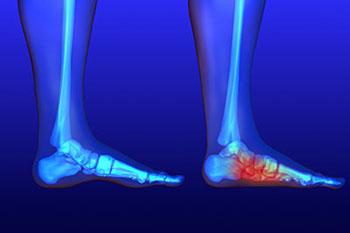

The feet serve as the foundation of the body. When pain is experienced, it’s therefore extremely important to identify early on what and where the issue is. The causes of foot pain vary greatly, including but not limited to diseases, deformities, improper footwear,...